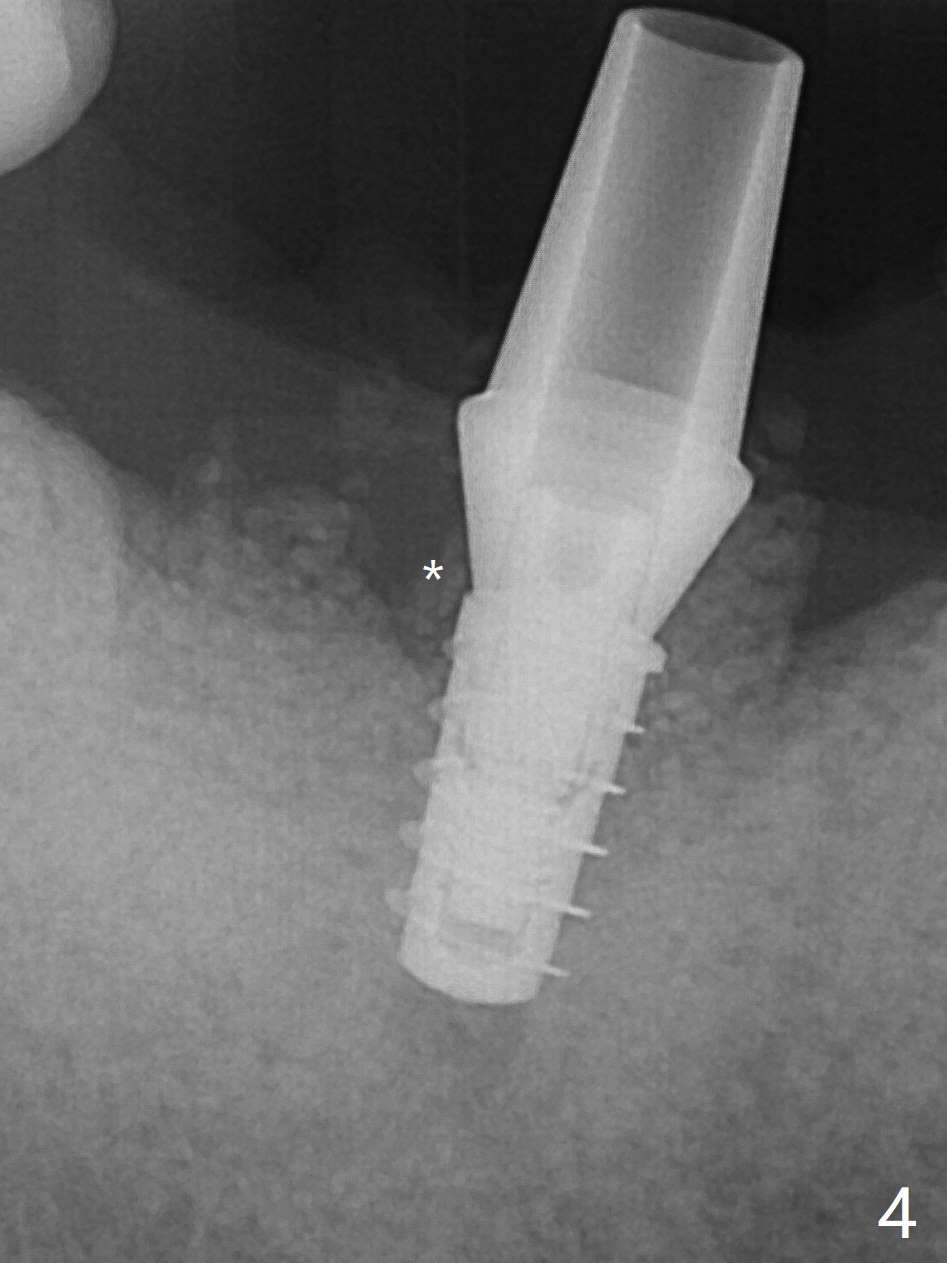

69岁男因疼痛回来拔除右下6,保留中隔牙龈,在近中牙槽窝开始钻洞(图一:空箭头),但是由于近中斜坡,最终1.6毫米先锋钻远中偏移。远中骨质高度减少,原先计划近中牙槽窝深度7毫米,当钻头滑到接近中隔,钻头尖口内接近神经,病人感到疼痛(浸润麻醉)。block anesthesia下,放置4x9毫米报废植体(图二),口内显得太长,所以选择4x7毫米植体(图三),基台就位。第一次放置骨粉远中不足(图四:*),再次植骨,好像达到目的(图五:*)。覆盖PRF膜后,放置树脂敷料(图六:A)。